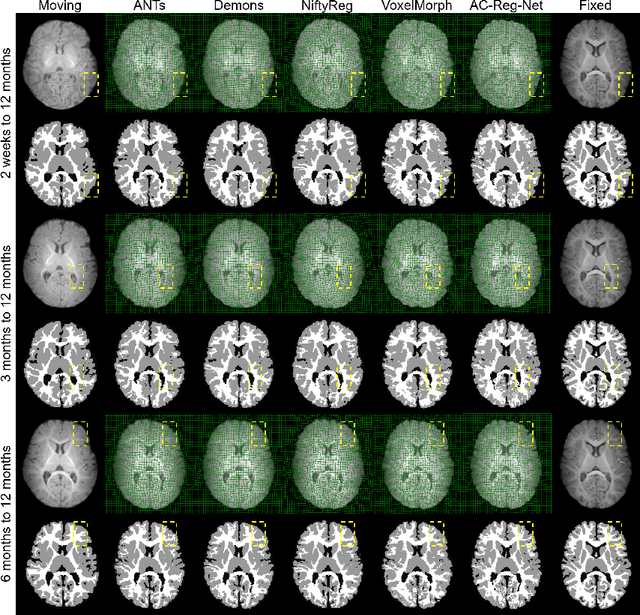

Deformable image registration is fundamental to longitudinal and population analysis. Geometric alignment of the infant brain MR images is challenging, owing to rapid changes in image appearance in association with brain development. In this paper, we propose an infant-dedicated deep registration network that uses the auto-context strategy to gradually refine the deformation fields to obtain highly accurate correspondences. Instead of training multiple registration networks, our method estimates the deformation fields by invoking a single network multiple times for iterative deformation refinement. The final deformation field is obtained by the incremental composition of the deformation fields. Experimental results in comparison with state-of-the-art registration methods indicate that our method achieves higher accuracy while at the same time preserves the smoothness of the deformation fields. Our implementation is available online.